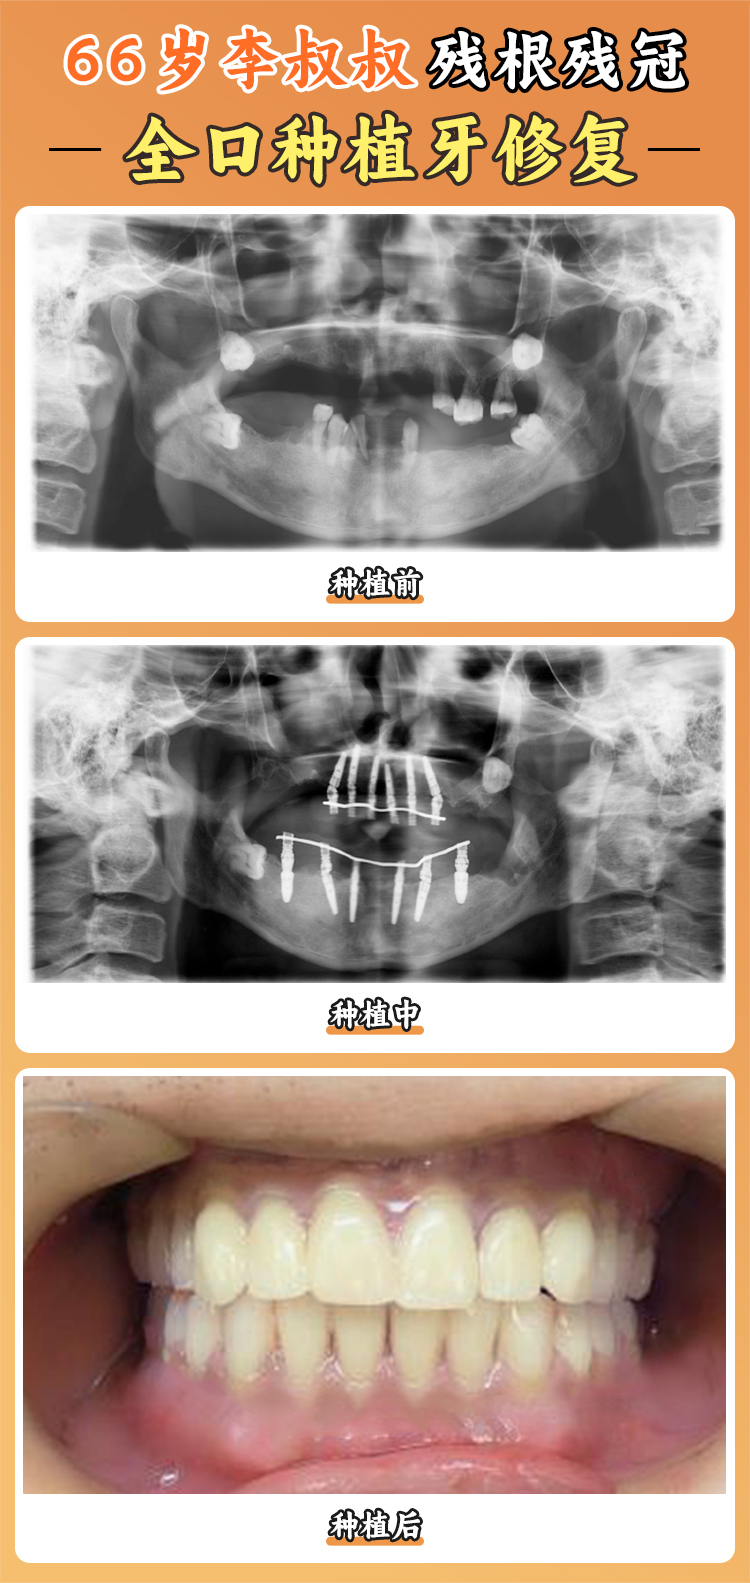

對(duì)于牙齒全部缺失的中老年人來說,**全口種植牙**是修復(fù)口腔功能和外觀的至佳方案。雖然全口種植的費(fèi)用較高,但它的舒適度和實(shí)用性遠(yuǎn)超傳統(tǒng)假牙。

在**上海西郊眾植口腔**,全口種植牙的價(jià)格如下:

• All-on-4種植系統(tǒng):8萬(wàn)元~12萬(wàn)元/上頜或下頜

• All-on-6種植系統(tǒng):10萬(wàn)元~16萬(wàn)元/上頜或下頜

• 傳統(tǒng)全口種植(10~12顆):15萬(wàn)元~25萬(wàn)元/全口